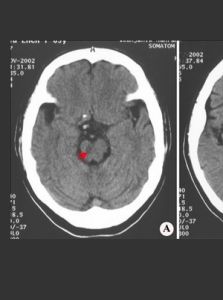

通過對患者顱腦進行細緻的掃描,配合彩色都卜勒影像儀來構建三維立體的腦部結構圖;將穿刺針、微電極等顯微器械置入腦內特定靶點,通過記錄電生理信號來確定需要進行手術的部位。